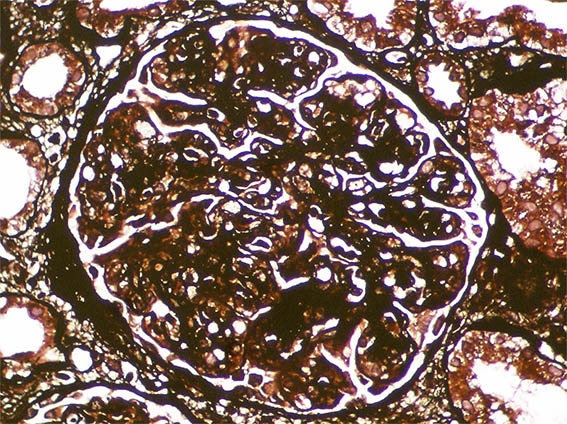

Figure 8. Methenamine-silver stain, X400.